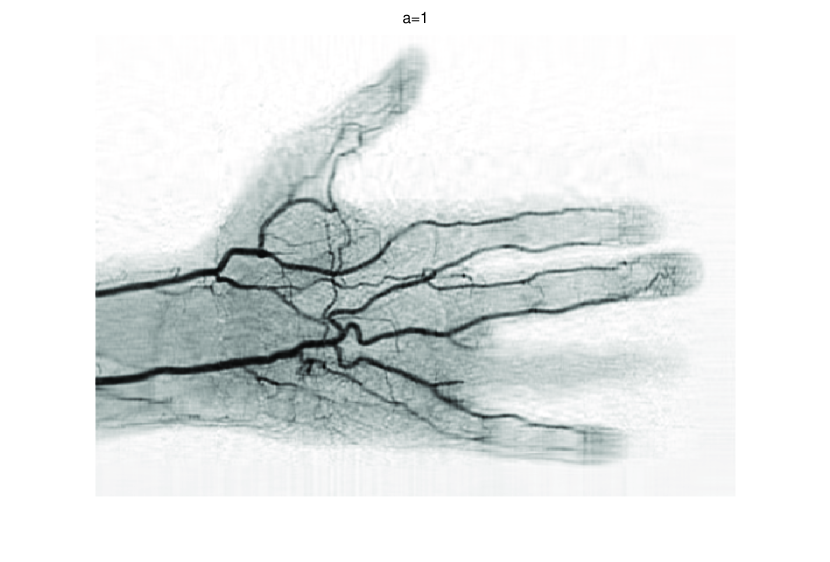

In this subsection, we demonstrate performances of ISVTA on image inpainting problems. The ISVTA is tested on some medical grace images (255×192255192255\times 192 Brain angiography image (BAI), 395×549395549395\times 549 Hand angiography image (HAI) and 419×400419400419\times 400 Intracranial venous image (IVI)). We use the SVD to obtain their approximated low-rank images with rank r=30,40,30𝑟304030r=30,40,30, respectively. Numerical results of ISVTA for theses low-rank image inpainting problems are reported in Table 5, 6, 7, 8.

Figure 4: Original 395×549395549395\times 549 HAI and its approximation with rank 40.

Figure 7: Comparisons of ISVTA, SVTA and SVPA for recovering the approximated low-rank HAI with SR=0.40.